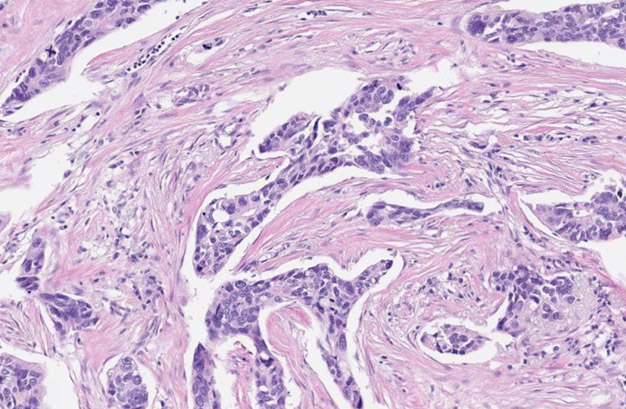

Fotos escaneadas de un tumor; se pueden ver células cancerosas que están coloreadas de morado. (Foto: Nucleai)